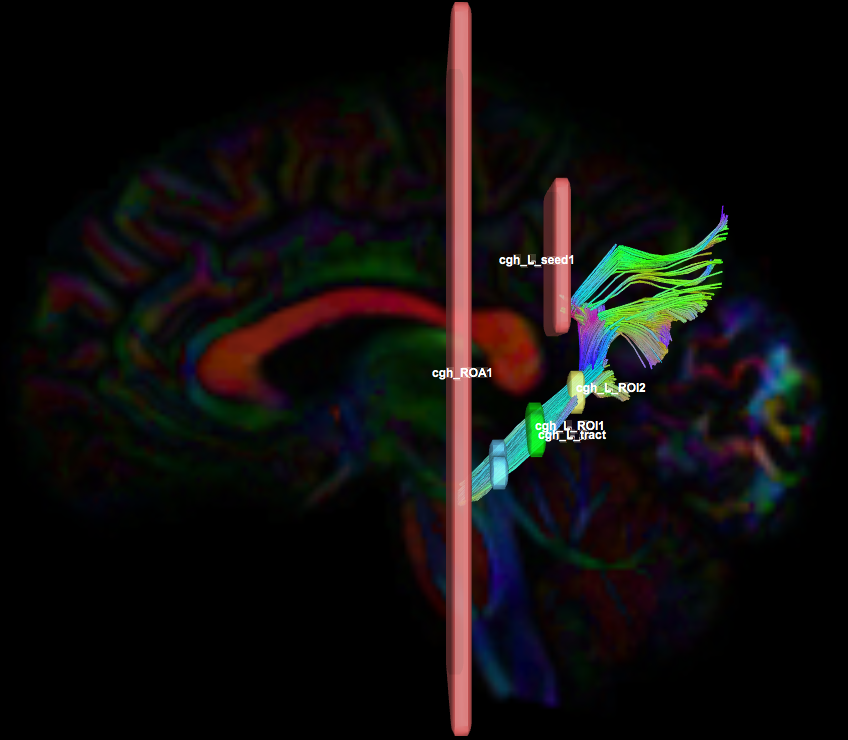

Instructions:

- Create two separate coronal seed regions (at approx. coronal slice 107): one for each side

- Create four separate coronal ROI regions (at approx. coronal slice 116 and 122): two for each side.

- Create one ROA region and draw a sagittal ROA slice at the midline (at approx. sagittal slice 78).

- Check the left seed/ROI regions and ROA region, then perform fiber tracking. Based on this output, the other ROA placements will be clearer.

- Using the same ROA file, draw 2-3 more regions:

- on a coronal slice anterior to seed/ROI regions (at approx. coronal slice 89)

- on optional coronal slices superior to the ROI regions.

- In the region list, check only the left seed region and ROA regions, then perform fiber tracking. Under the tract list, make sure only the desired left tract is checked and highlighted in purple. Save region, tract, and density files.

- Uncheck the left seed region and check the right seed region and ROA region, then perform fiber tracking. Under the tract list, make sure only the desired right tract is checked and highlighted in purple. Save region, tract, and density files.